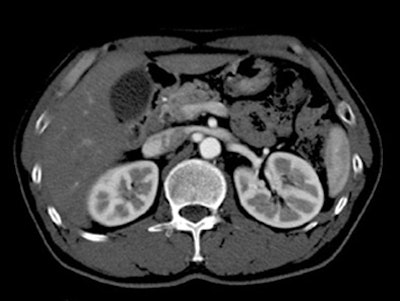

| Above, 55-second delay (nephrographic phase) seen in 51-year-old female patient. |